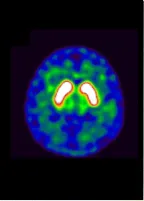

■MIBG心筋シンチグラフィー

パーキンソン病の患者さんでは、MIBGの心筋への取り込みが低下している。

正常

パーキンソン病